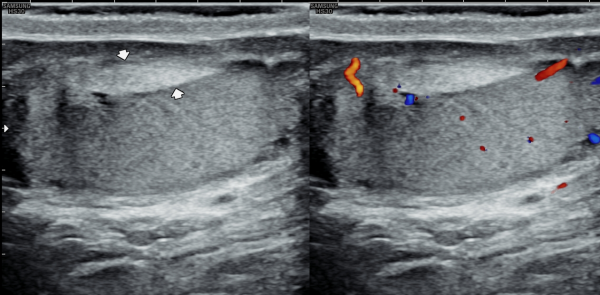

수년전부터 회음부에 통증이 있고 빈뇨가 심하다고 내원 당일 검사한 경직장 전립선 초음파 사진상 사정관의 낭종과 사정관이 좁아지고 있는 자료입니다.

A transrectal prostate ultrasound image taken on the day of the visit shows a cyst in the ejaculatory duct

and narrowing of the duct in a patient who had been experiencing perineal pain and severe urinary frequency for several years.